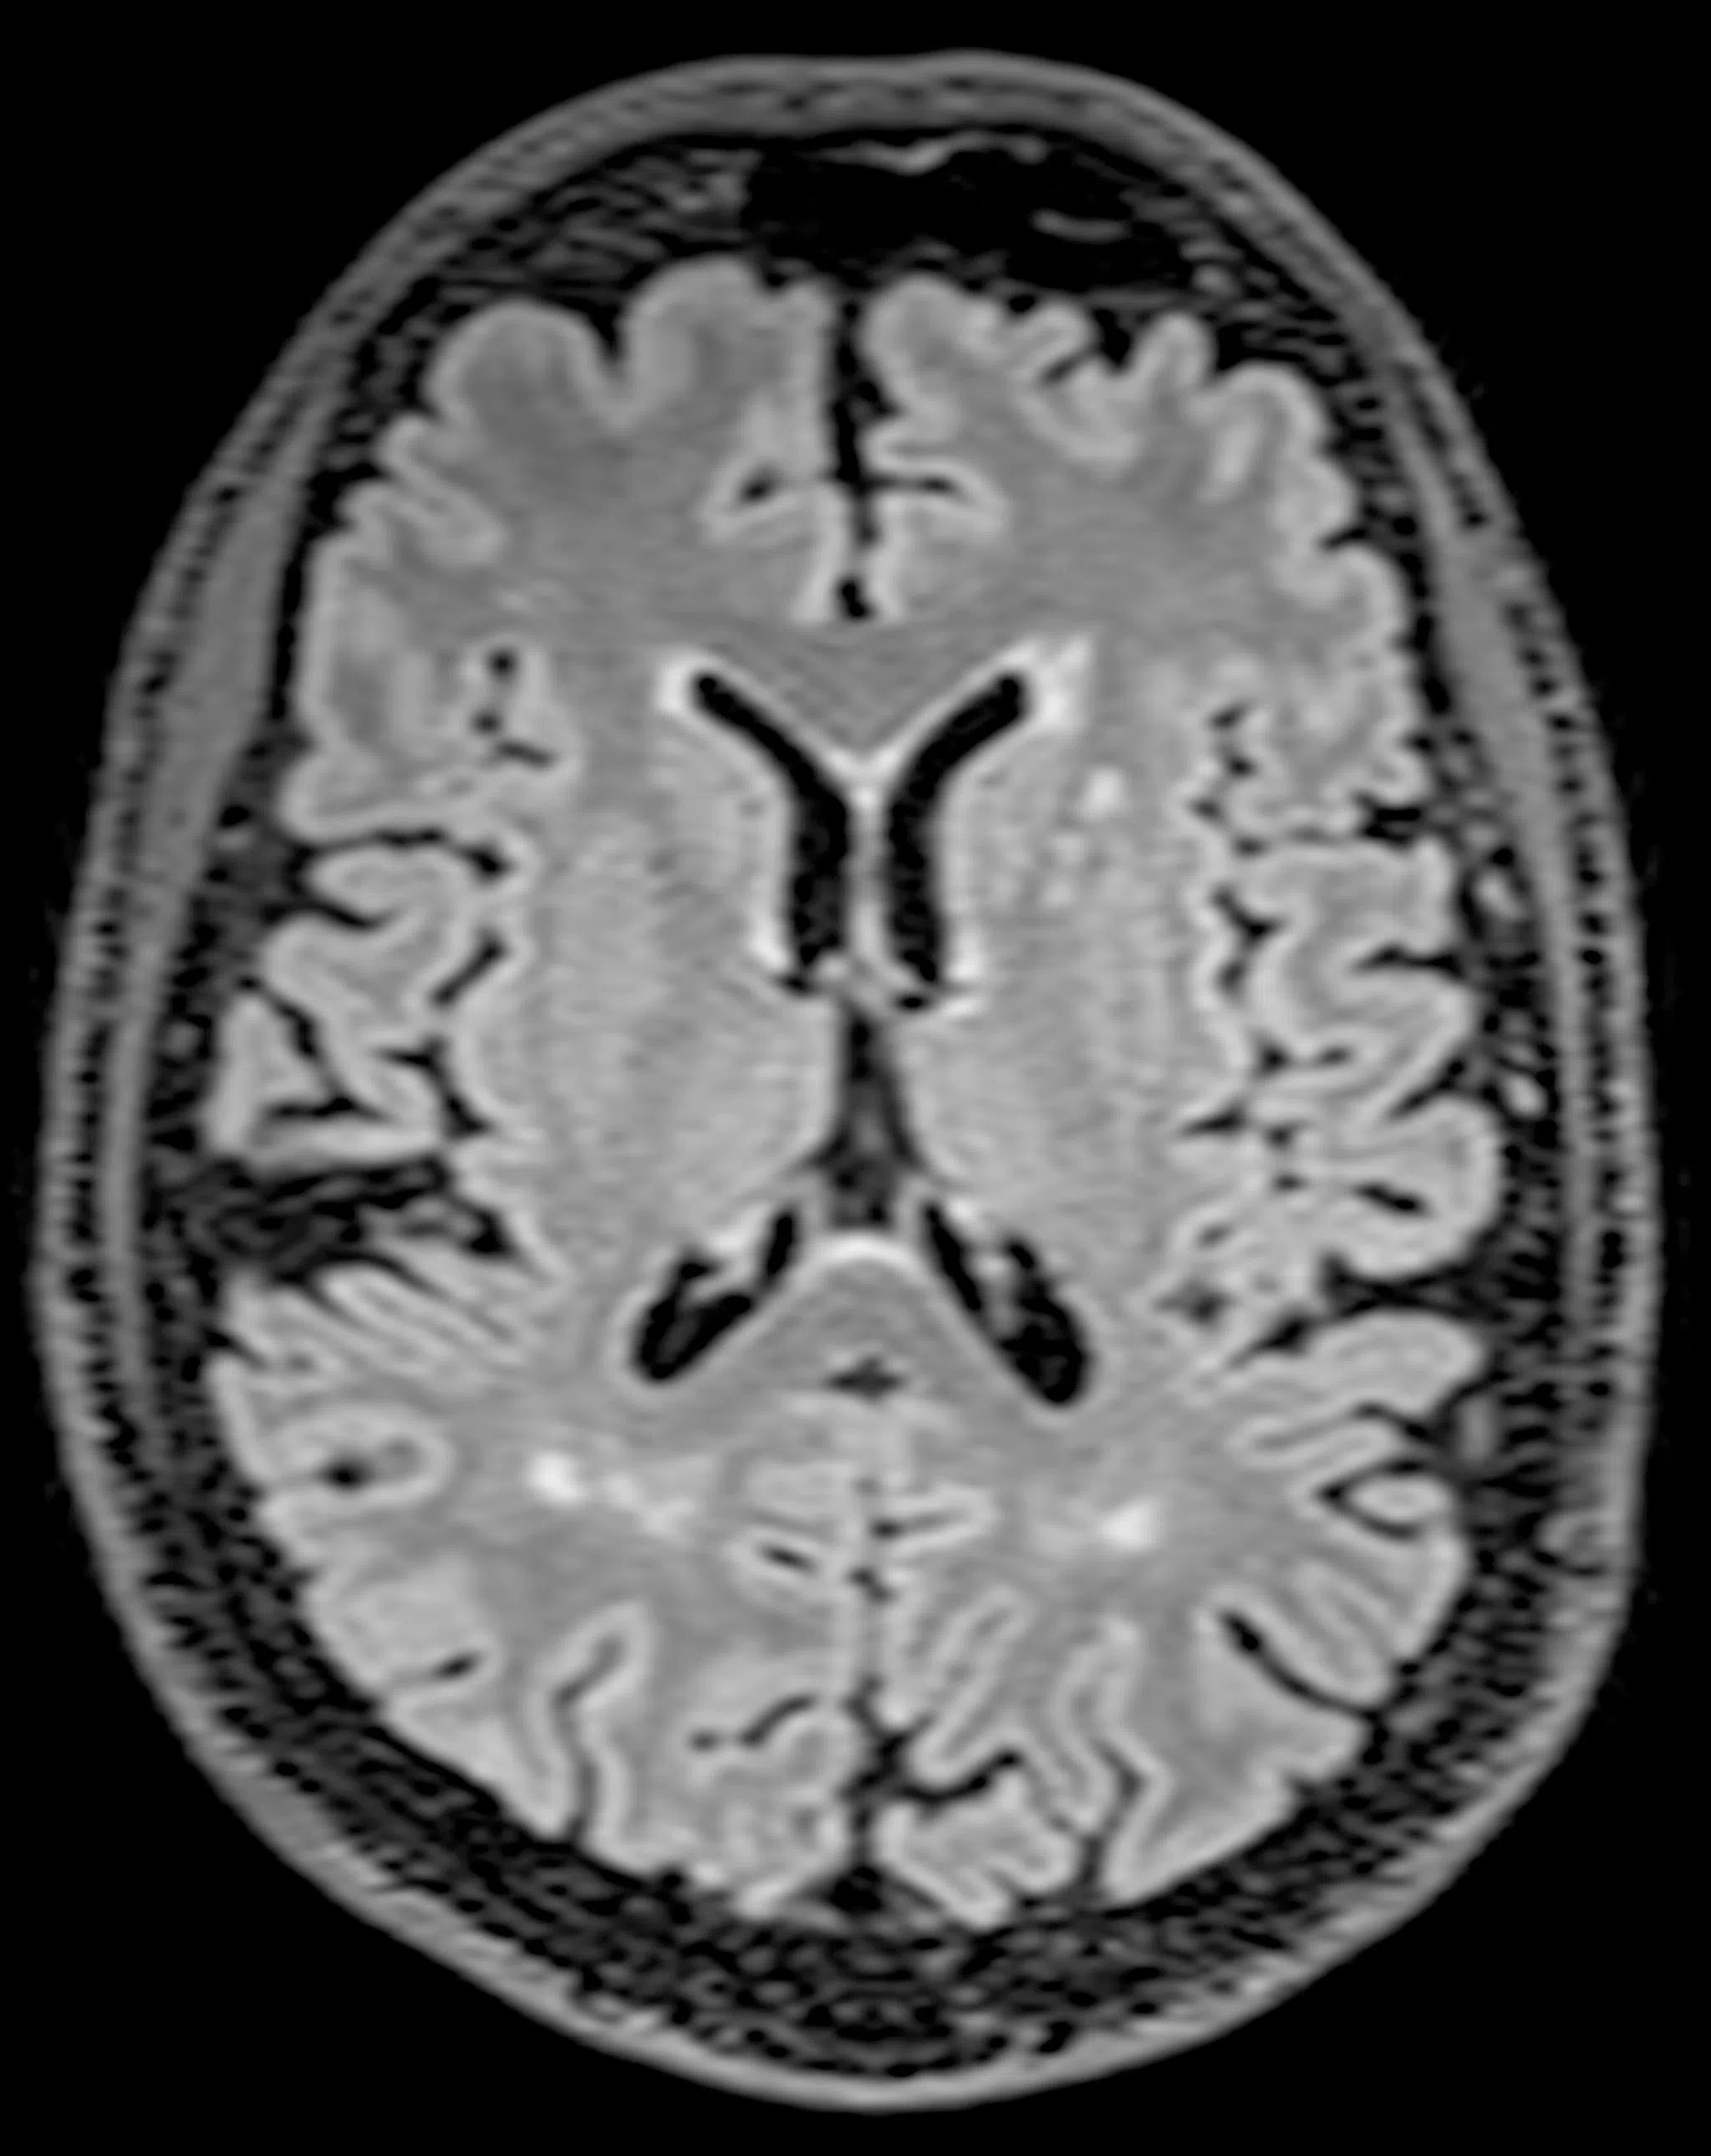

Her MRI scans revealed white matter in her brain, indicating potential risk factors that may require medical attention.

An MRI scan showing higher presence of white spots or “white matter hyperintensity”, a risk factor for mild cognitive impairment in early stages of dementia.

PHOTO: DEMENTIA RESEARCH CENTRE (SINGAPORE)

Preliminary findings, as well as emerging studies conducted in Asia, have found that Asian patients are three times more likely than Caucasians to suffer from silent strokes as a result of a condition of the narrowing of the small blood vessels which appear as lesions or “white matter hyperintensity” in brain scans.